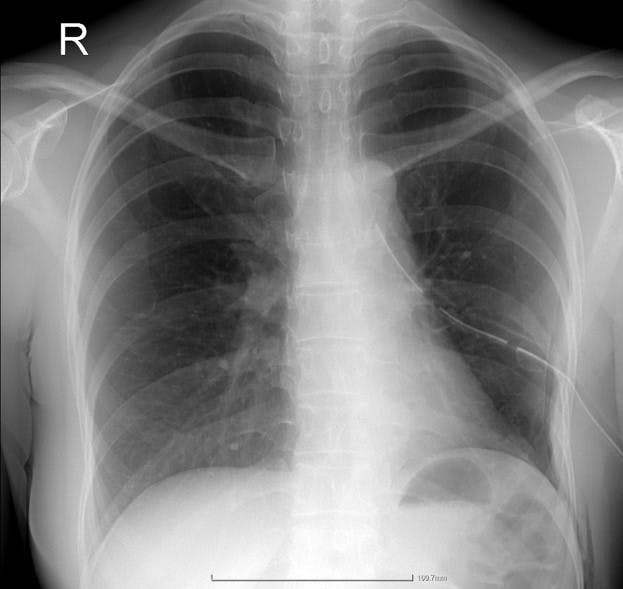

Radiografia postoperatorie a arătat o expansionare pulmonară completă a lobului superior restant, iar pacienta a fost externată după doar trei zile, beneficiind de o recuperare rapidă și de protecția oncologică oferită de rezecția completă.